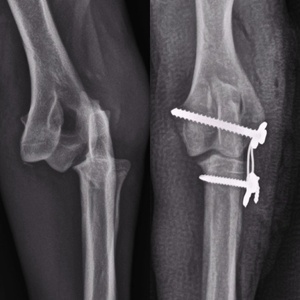

گالری تصاویر

رادیولوژی و سونوگرافی حیوانات در تهران